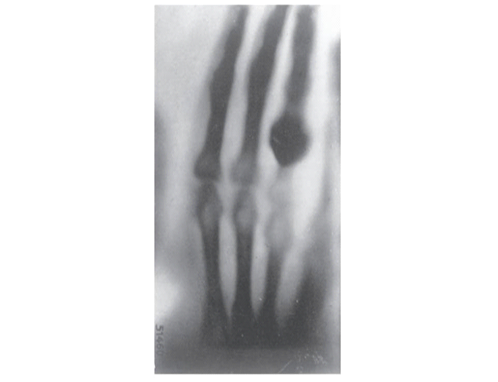

Em 23 de janeiro de 1896, Roentgen fez sua primeira demonstração prática em público na Sociedade de Física Médica de Würzburg, radiografando a mão do anatomista Albert von Kӧlliker, o que gerou grande entusiasmo entre os presentes. A descoberta recebeu ampla cobertura jornalística e sua popularização continuou. Em fevereiro de 1896, Roentgen enviou radiografias de um braço fraturado ao British Medical Journal para demonstrar o poder diagnóstico dos raios X. Em poucos meses, centros urbanos nos Estados Unidos já tinham acesso à descoberta. O impacto foi tão significativo que durante o ano de 1896 foram publicados mais de 1000 artigos e 49 livros sobre os raios X, com o primeiro artigo publicado por um pesquisador não europeu aparecendo na revista Science, nos Estados Unidos (Lima, Afonso, Pimentel, 2009).

Imagem 2 - Impressão fotográfica da radiografia da mão do professor von Kolliker, apresentada por Röntgen em 23 de janeiro de 1896 (Brogdon, 2011, p.12).